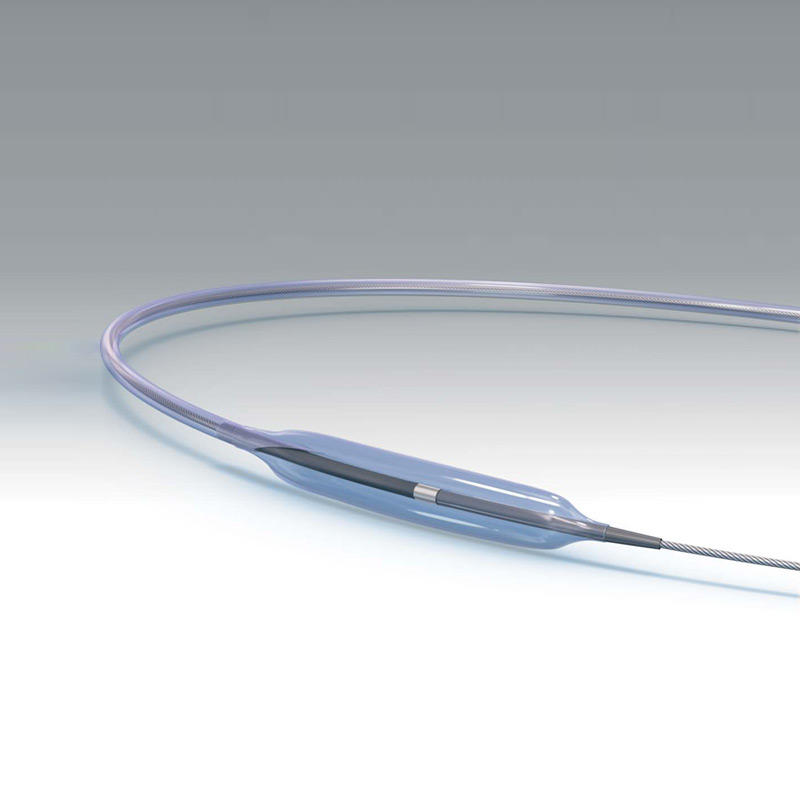

Cruiser / Teleflex (BIOTRONIK Vascular Intervenion)

Coronary Guide Wire Indicated for PTCA applications